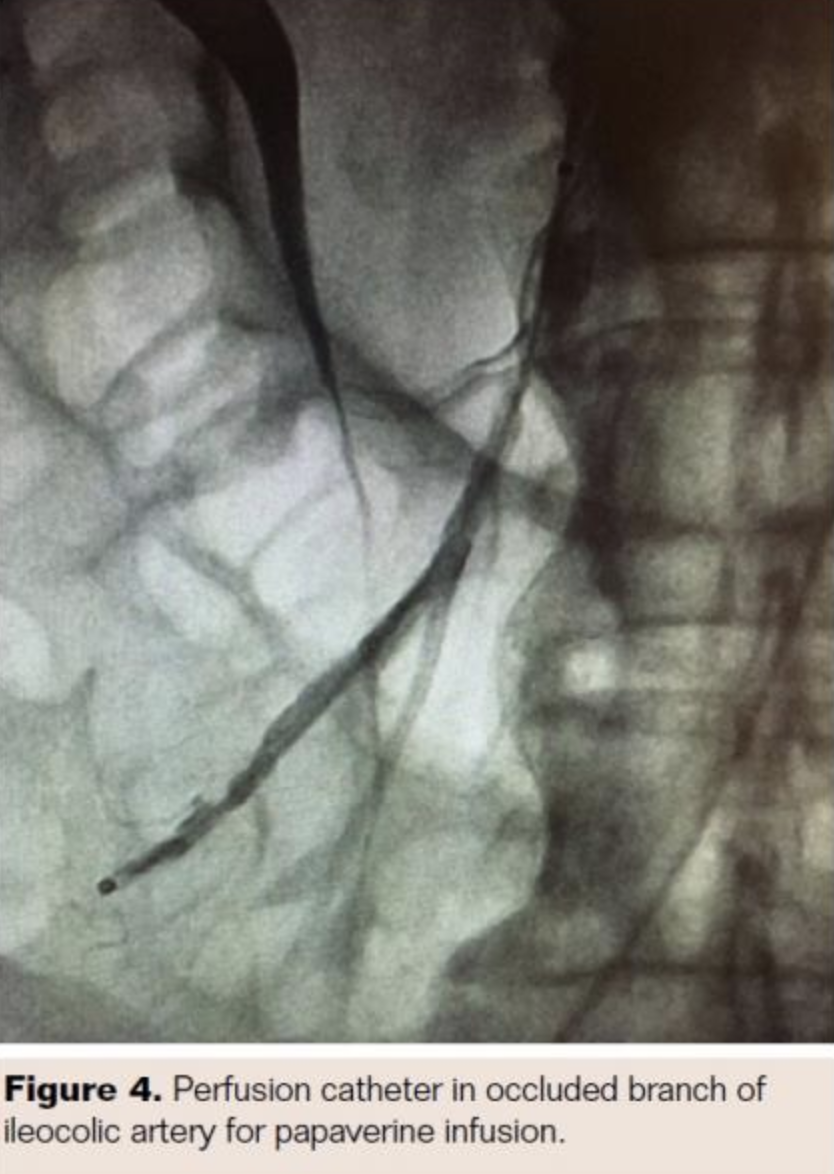

The patient was taken for urgent angiography due to rapid rise in biomarkers reflecting early bowel necrosis. Right femoral artery access was obtained and cannulated with a 6 Fr sheath. A 4 Fr internal mammary catheter was used to cannulate the superior mesenteric artery (SMA). The catheter was advanced into the proximal segment of the vessel over a Glidewire (Terumo). Angiography via the internal mammary catheter confirmed the CT angiographic findings. This catheter was exchanged for a 6 Fr, 55 cm Ansel guiding sheath (Cook Medical). Activated clotting time was 177 seconds, and heparin 3,000 U bolus was administered intravenously. A 0.014˝ wire was advanced through the occluded distal SMA and thrombectomy was done using an Angiojet XVG thrombectomy catheter with complete resolution of the thrombus (Figure 2). The wire was then advanced into the ileocolic artery, which was treated with a similar technique (Figure 3). The proximal segment of the ileocolic artery showed thrombus resolution but a large branch of this vessel was still occluded. Thrombectomy in this branch did not re-establish flow in the vessel, and the angiographic appearance was consistent with diffuse spasm. A 135 cm Cragg-Mcnamara Valved Infusion Catheter (Medtronic) with 10 cm infusion length was then advanced into this branch (Figure 4) and intra-arterial papaverine was administered via this catheter at 30 mg/hr. An intravenous heparin drip was administered peripherally at 500 U/hr.